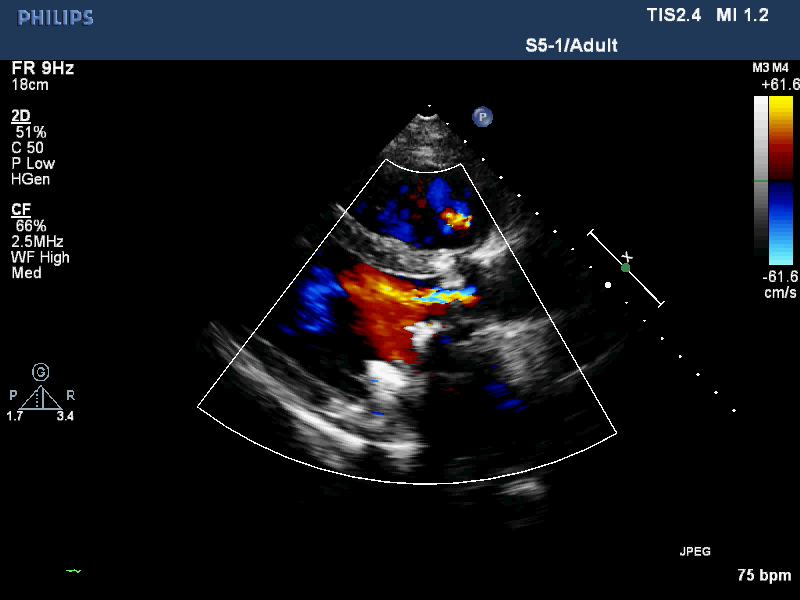

术后超声检查

术后转归

该手术全程顺利,总用时122min,患者术后当天血红蛋白尿消失,无明显瓣周漏,无卡瓣及传导阻滞发生,患者恢复良好,胸闷气短症状消失,并于术后5天出院。